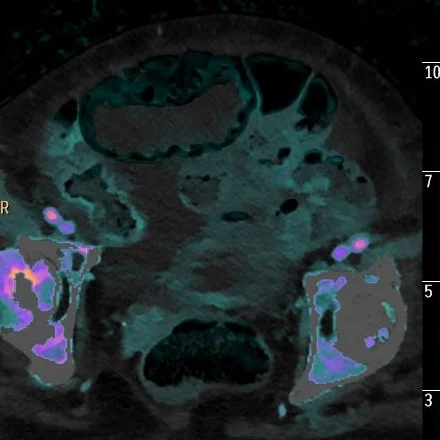

Iodine overlay: Nicely depicts perfusion to these loops.